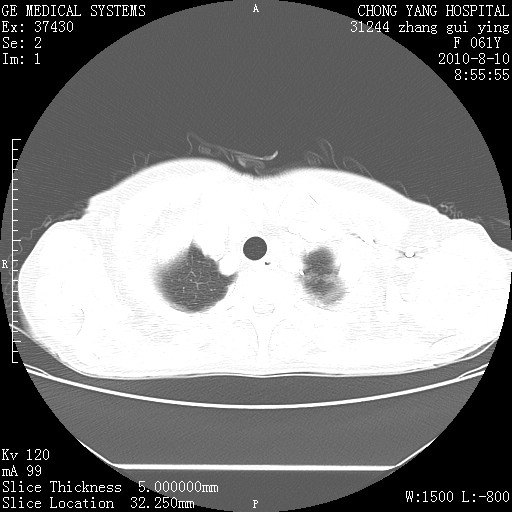

标题: CT28314:F61Y胸部增强,发热咳嗽一周入院,后面的为一周前平 [打印本页]

标题: CT28314:F61Y胸部增强,发热咳嗽一周入院,后面的为一周前平

1、支持考虑右侧中央型肺癌伴右肺中叶节段性不张及下叶支气管黏液痰栓    2、左肺上叶舌段感染。

支持右下肺中央型肺癌并左上肺感染.

确切的说:1:右肺下叶中心型肺癌侵及中叶支气管并中叶不张,纵膈淋巴结转移。2:左肺舌叶炎症。3:右侧胸腔少量积液

1:右肺下叶中心型肺癌侵及中叶支气管并中叶不张,纵膈淋巴结转移。2:左肺舌叶炎症。3:右侧胸腔少量积液。支持!

右肺下叶中心型肺癌侵及中叶支气管并中叶不张,纵膈淋巴结转移。2:左肺舌叶炎症。3:右侧胸腔少量积液